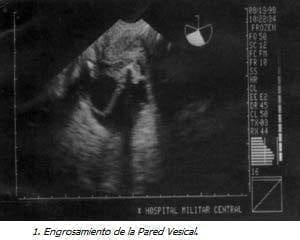

Con Impresión Diagnóstica de dolor abdominal a estudio y embarazo de 18 semanas se realiza ecografía obstétrica que evidencia feto único, vivo, con biometría para 18 semanas, ausencia del líquido amniótico y distensión abdominal importante. Se realizó ecografía de detalle previa cordocentesis para cariotipo y amnioinfusión de SSN, observando marcada ascitis, dilatación vesical importante con engrosamiento de la pared y dos soluciones de continuidad, dilatación de la uretra proximal y aumento de tamaño e hiperecogenicidad renal bilateral, los ureteres no se evidenciaron excepto en la unión vesicoureteral. El resultado del estudio genético confirmó sexo masculino (46XY) sin ninguna malformación genética asociada.

La obstrucción del nivel uretral secundario a valvas posteriores tiene un amplio espectro de características ecográficas y los signos cardinales consisten en dilatación persistente de la vejiga y la porción proximal de la uretra, engrosamiento de la pared vesical mayor de 2mm, los uréteres están característicamente dilatados y tortuosos y en casos severos su entrada a la vejiga se observa (10-15).